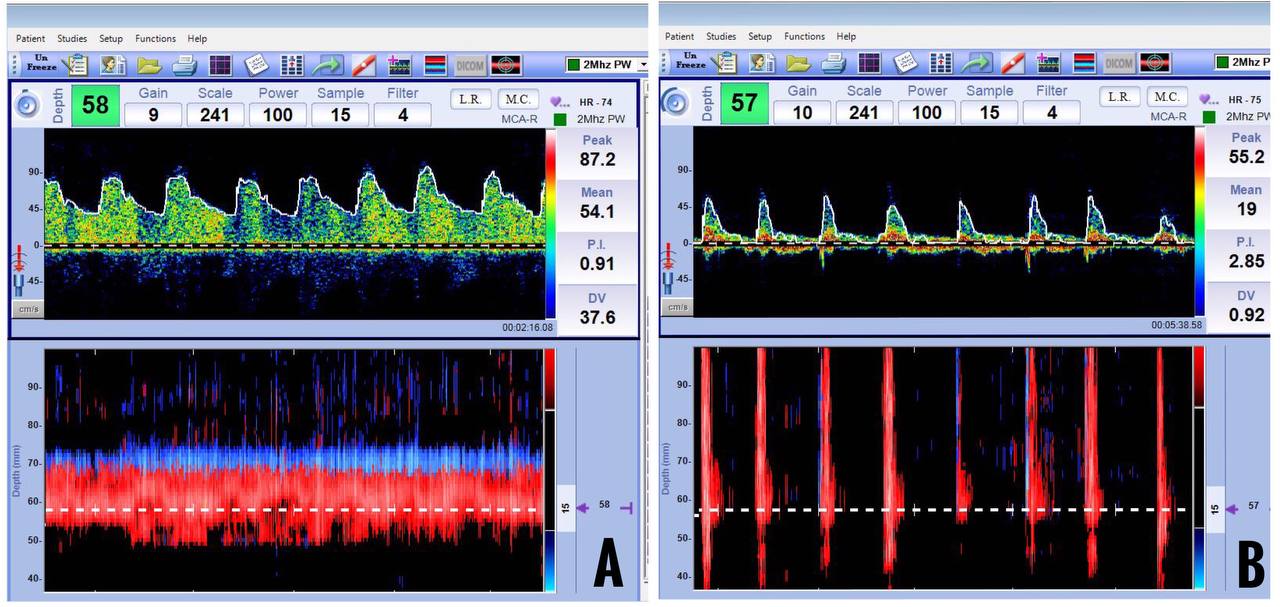

An increase in ICP causes elevated cerebrovascular resistance in the distal blood vessels. This manifests as an initial increase in PSV, a decrease in EDV, and an increase in the PI in the TCD. EDV reaches baseline when ICP equals diastolic pressure. In case of a further increase in the ICP equalling systolic pressure, oscillating flow is observed, wherein forward and reverse flow components in one cardiac cycle exhibit almost the same area. Systolic spikes are seen when ICP is more than systolic pressure, which is highly suggestive of cerebral circulatory arrest when present bilaterally. They are sharp unidirectional velocity signals in early systole of less than 200 ms duration, less than 50 cm/sec, and without a flow signal during the remaining cardiac cycle. Gradually, systolic spikes will disappear, and no flow signals can be observed (Figure 16).

(A) Decrease in mean flow velocity and end-diastolic velocity, (B) Diastolic flow reversal, (C) Waveforms resembling systolic spikes, (D) No flow state

The TCD is used as an ancillary test for the assessment of CCA. It is initiated when clinical examination suggests the absence of cerebral and brainstem functions. TCD findings are suggestive of cerebral circulatory arrest when:23

- Bilateral MCA insonation reveals an oscillating pattern, systolic spike, or absent flow signals.

- Bilateral extracranial ICA insonation reveals an oscillating pattern.

- Similar findings are obtained in the second examination done at an interval of at least 30 minutes.